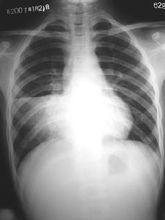

大葉肺炎 早期咳嗽多不重,無痰,以後可見有咳鐵鏽色痰,病程1周后尚可聽到濕性羅音。胸部X線片典型改變為一個肺葉或肺段的大片陰影,均勻緻密,右上葉或左下葉最為多見,可伴有胸腔積液。其它化驗室檢查可見白細胞及中性粒細胞明顯增高,C反應蛋白陽性,肺炎鏈球菌病原學檢測方法包括:血液、氣道分泌物、胸水的細菌培養,血、尿細菌莢膜抗原檢測,特異性抗體的檢測等。如獲得陽性結果是對診斷的有力支持。

大葉肺炎 疾病早期,患者因毒血症而出現高熱、寒戰,外周血白細胞計數增高。因肺泡腔內有漿液性滲出物,故聽診可聞及濕性囉音,X線檢查肺紋理增粗。當肺組織發生實變時,臨床上則出現叩診呈濁音、觸覺語顫增強及支氣管呼吸音等典型實變體徵。由於肺泡腔充滿滲出物,使肺泡換氣功能下降,出現發紺等缺氧症狀及呼吸困難。以後滲出物中的紅細胞被巨噬細胞吞噬、破壞,形成含鐵血黃素混於痰中,使痰液呈鐵鏽色。隨著肺泡腔中紅細胞被大量纖維素和嗜中性粒細胞取代,痰液的鐵鏽色消失。並發纖維素性胸膜炎時可出現胸痛,聽診可聞及胸膜摩擦音。X線檢查可見段性或大葉性分布的均勻密度增高陰影。隨著病原菌被消滅,滲出物溶解、液化和清除,臨床症狀減輕,肺實變灶消失。X線表現為散在不均勻的片狀陰影。若不出現併發症,本病的自然病程為2周左右,若早期套用抗生素可縮短病程。

10.胸部X線檢查顯示段或葉性均勻一致的大片狀密度增高陰影。

5、胸部X線檢查顯示段或葉性均勻一致的大片狀密度增高陰影。